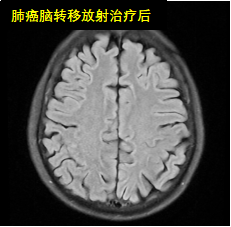

放射治疗是利用高能放射线消灭肿瘤的原发灶或转移灶的一种局部治疗方法。是治疗恶性肿瘤的三大手段之一,具有无创、副作用小、适应范围广、肿瘤局部控制率高等优点。适应症:全身各部位早、中、晚期恶性肿瘤。